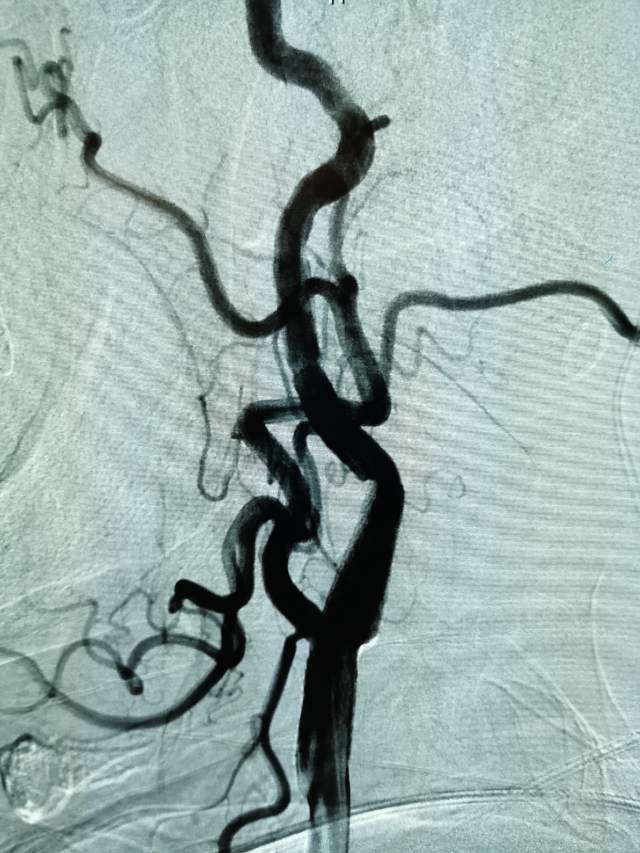

进一步行DSA检查后发现:左侧颈内动脉起始部有一个颈动脉蹼。这个血管内的“蹼”,是一个薄片状的结构,类似掌部的“蹼”,它会在颈内动脉起始部产生“扰流效应”,瘀滞的血流存在栓子形成和脱落的风险………,冲散的栓子可以“天女散花”,也可以“天上掉下石头”,这不,这位兄弟就被掉下的石头砸到颅内的功能区了,手脚语言都砸坏了。